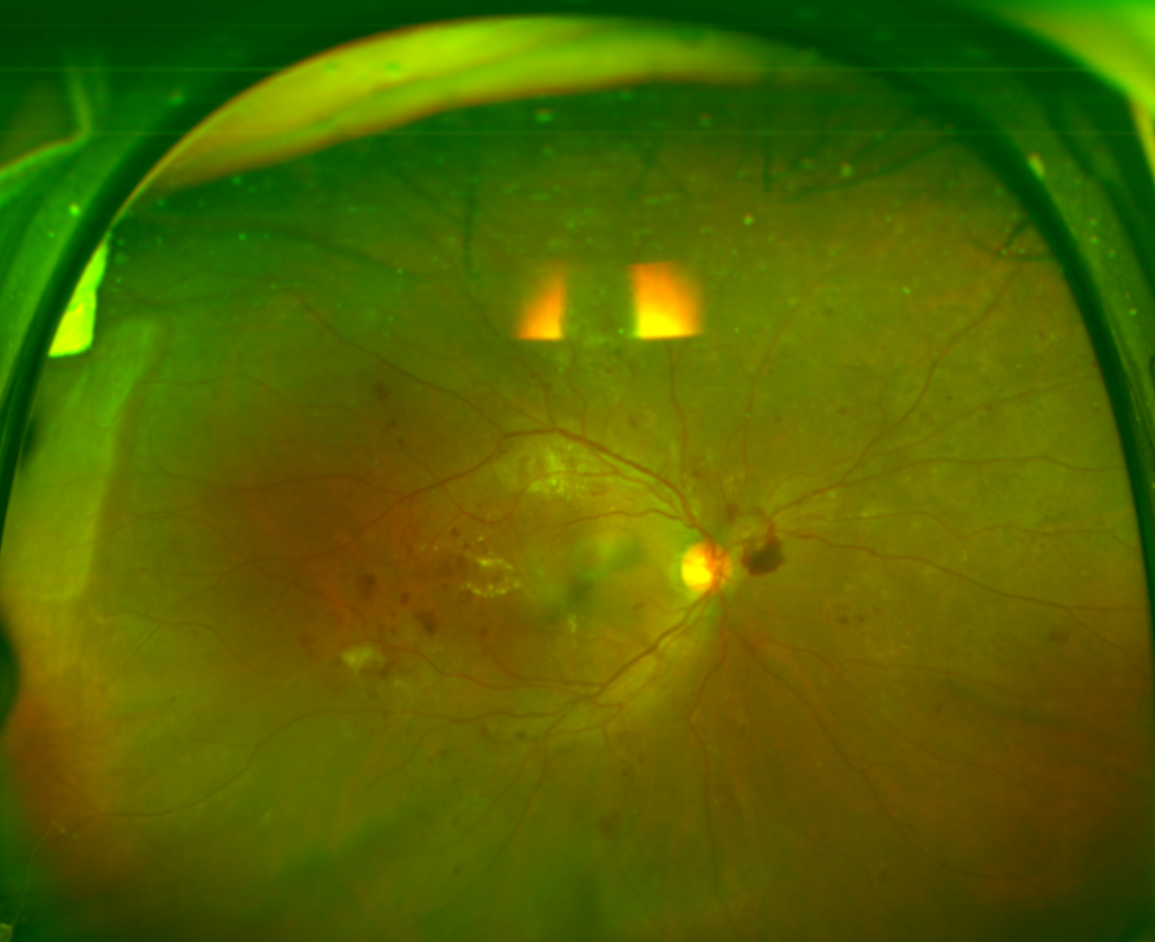

糖尿病视网膜病变是糖尿病常见的并发症,近年来患病群体逐渐年轻化。糖尿病患者的视网膜小血管长期处于高糖环境中,会变得像有裂缝的水管一样脆弱,容易出现渗漏情况。

为了获取更多氧气,视网膜会增生新的血管,但这些新生血管质地脆弱,极易破裂出血,进而引发玻璃体积血、机化等问题,严重时可能导致视网膜脱离,甚至失明。

(▲“糖网”眼底)